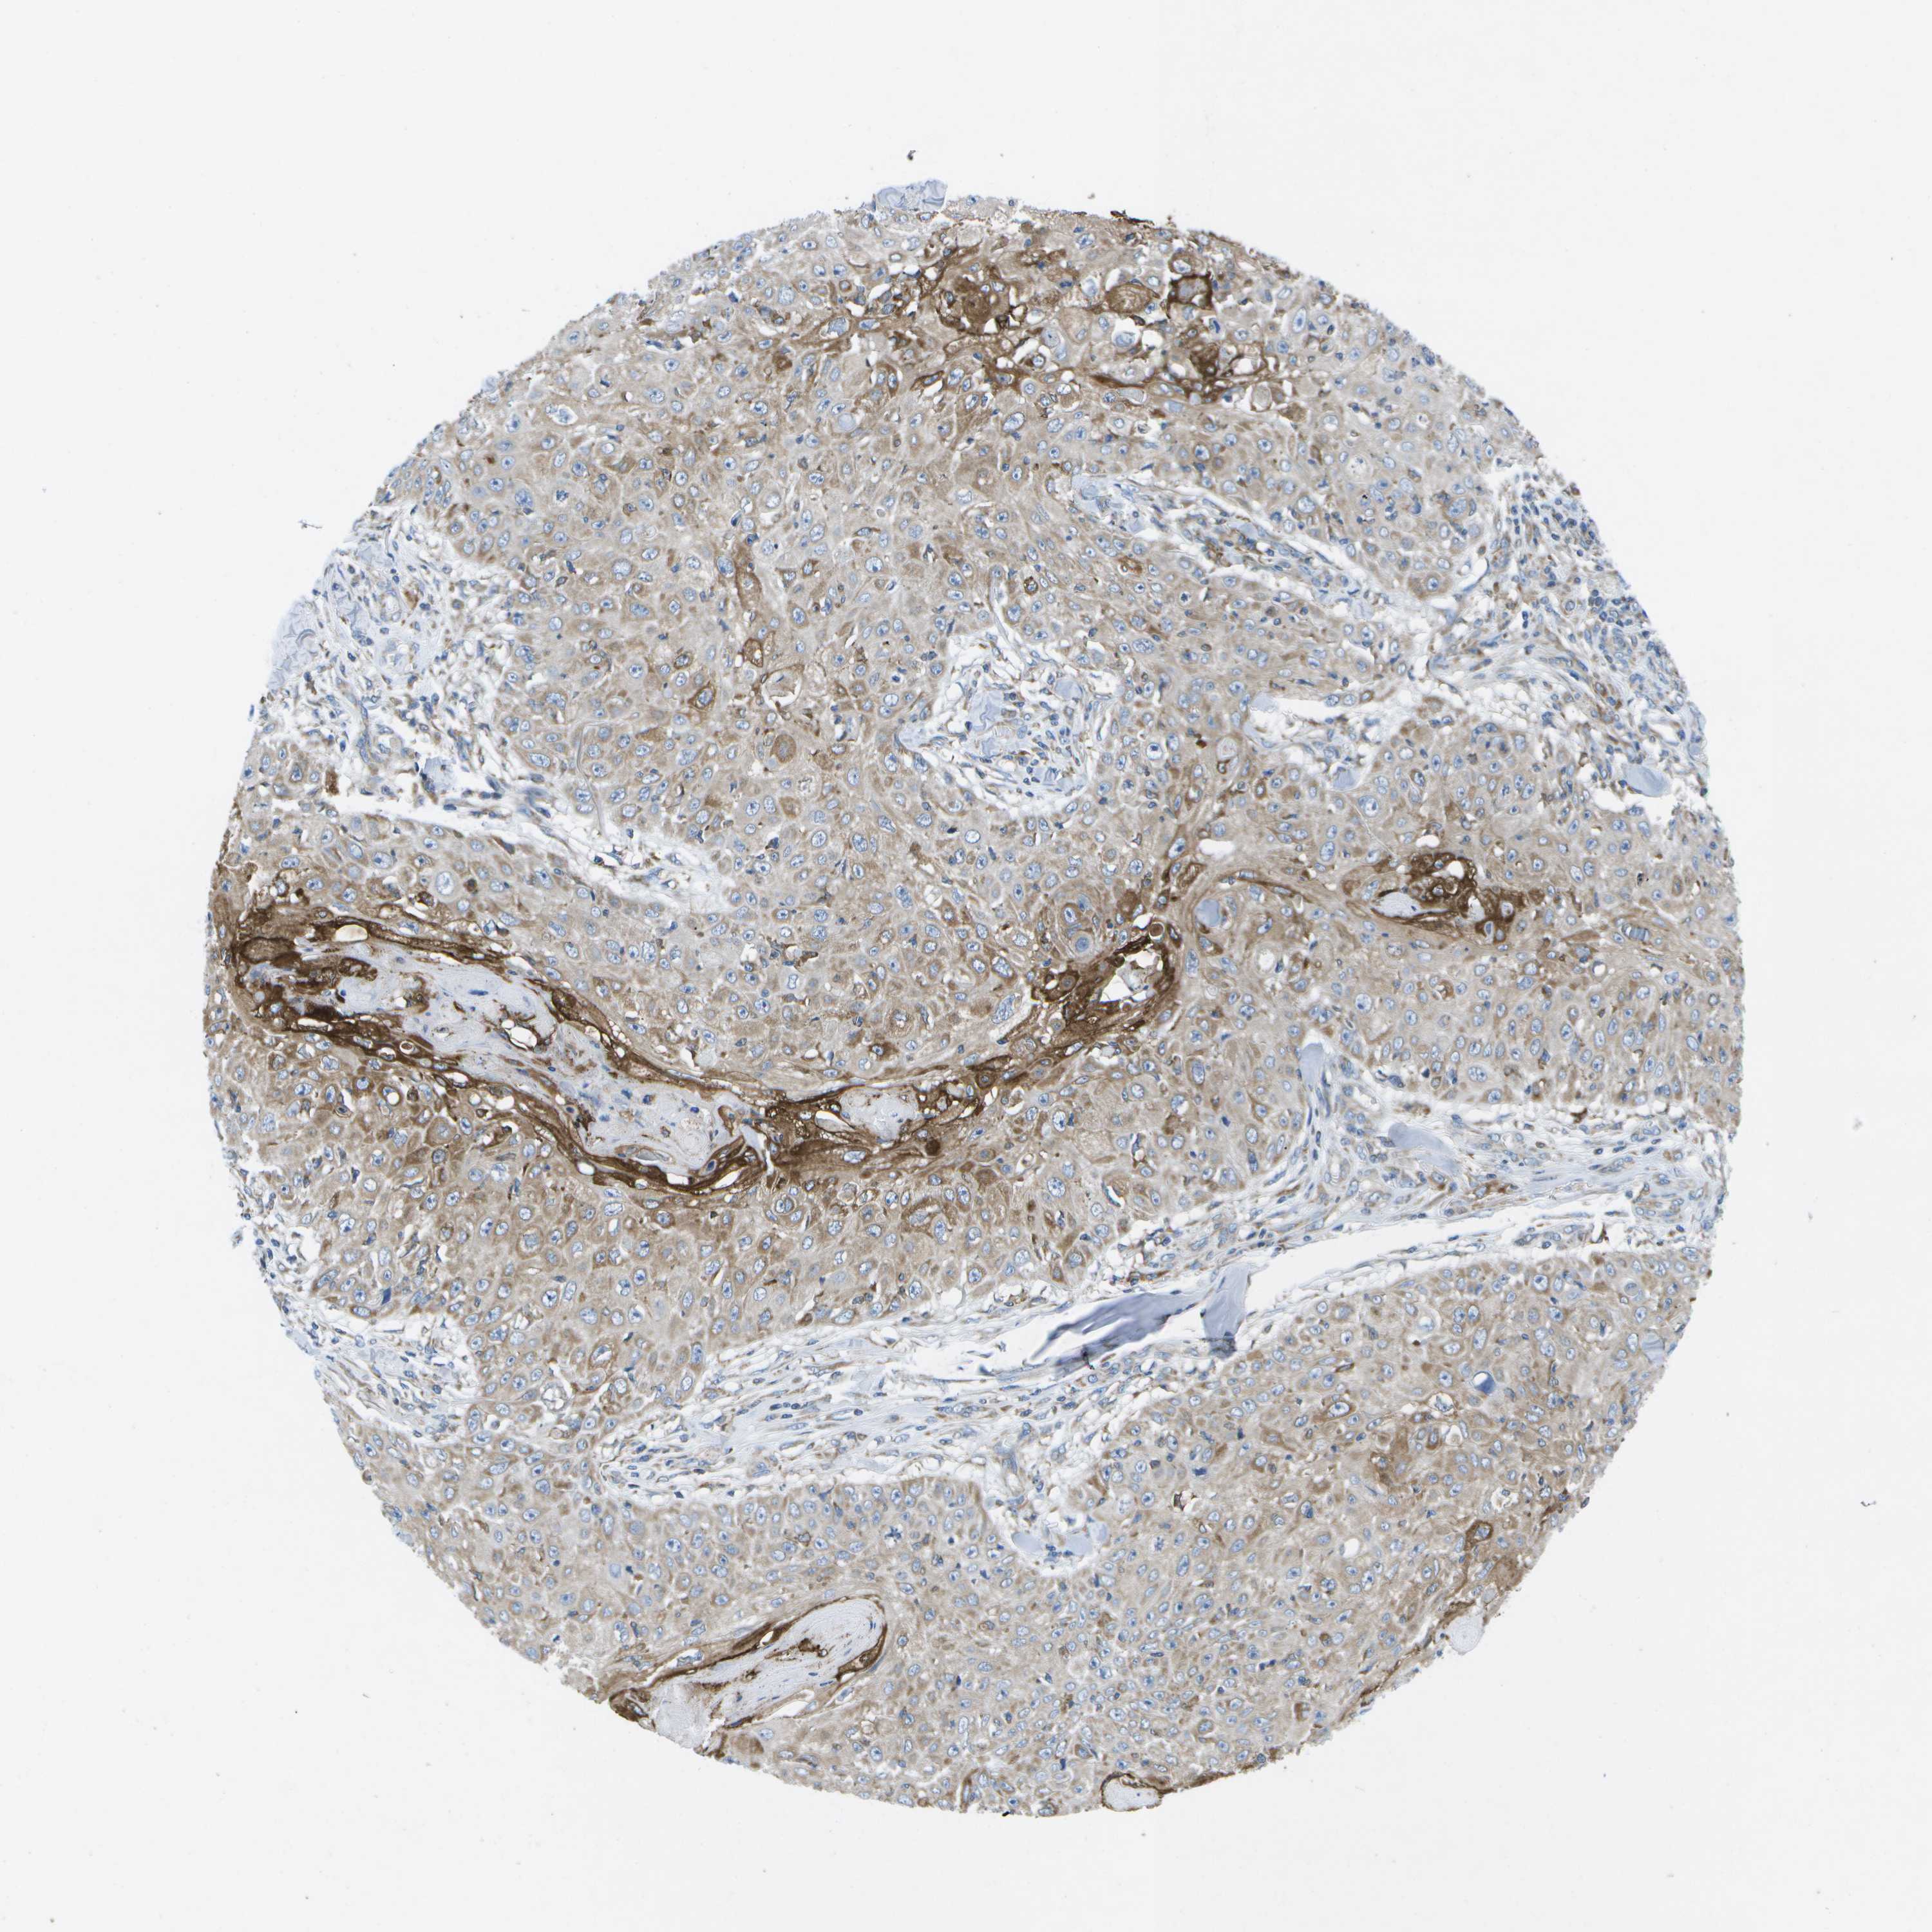

SKIN CANCER - Protein expressioni

A mouse-over function shows sample information and annotation data. Click on an image to view it in a full screen mode. Samples can be filtered based on level of antibody staining by selecting one or several of the following categories: high, medium, low and not detected. The assay and annotation is described here.

Antibody stainingi

Antibody staining in the annotated cell types in the current human tissue is reported as not detected, low, medium, or high, based on conventional immunohistochemistry profiling in selected tissues. This score is based on the combination of the staining intensity and fraction of stained cells.

Each image is clickable and will lead to virtual microscopy that enables deeper exploration of all samples and also displays staining intensity scores, fraction scores and subcellular localization as well as patient and tissue information for each sample.

Antibody HPA015648

Staining

High

Medium

Low

Not detected

Intensity

Strong

Moderate

Weak

Negative

Quantity

>75%

75%-25%

<25%

None

Location

Nuclear

Cytoplasmic/membranous

Cytoplasmic/membranous,nuclear

Squamous cell carcinoma in situ, NOS

Squamous cell carcinoma, NOS

Squamous cell carcinoma, metastatic, NOS

Basal cell carcinoma

Adnexal tumor, benign